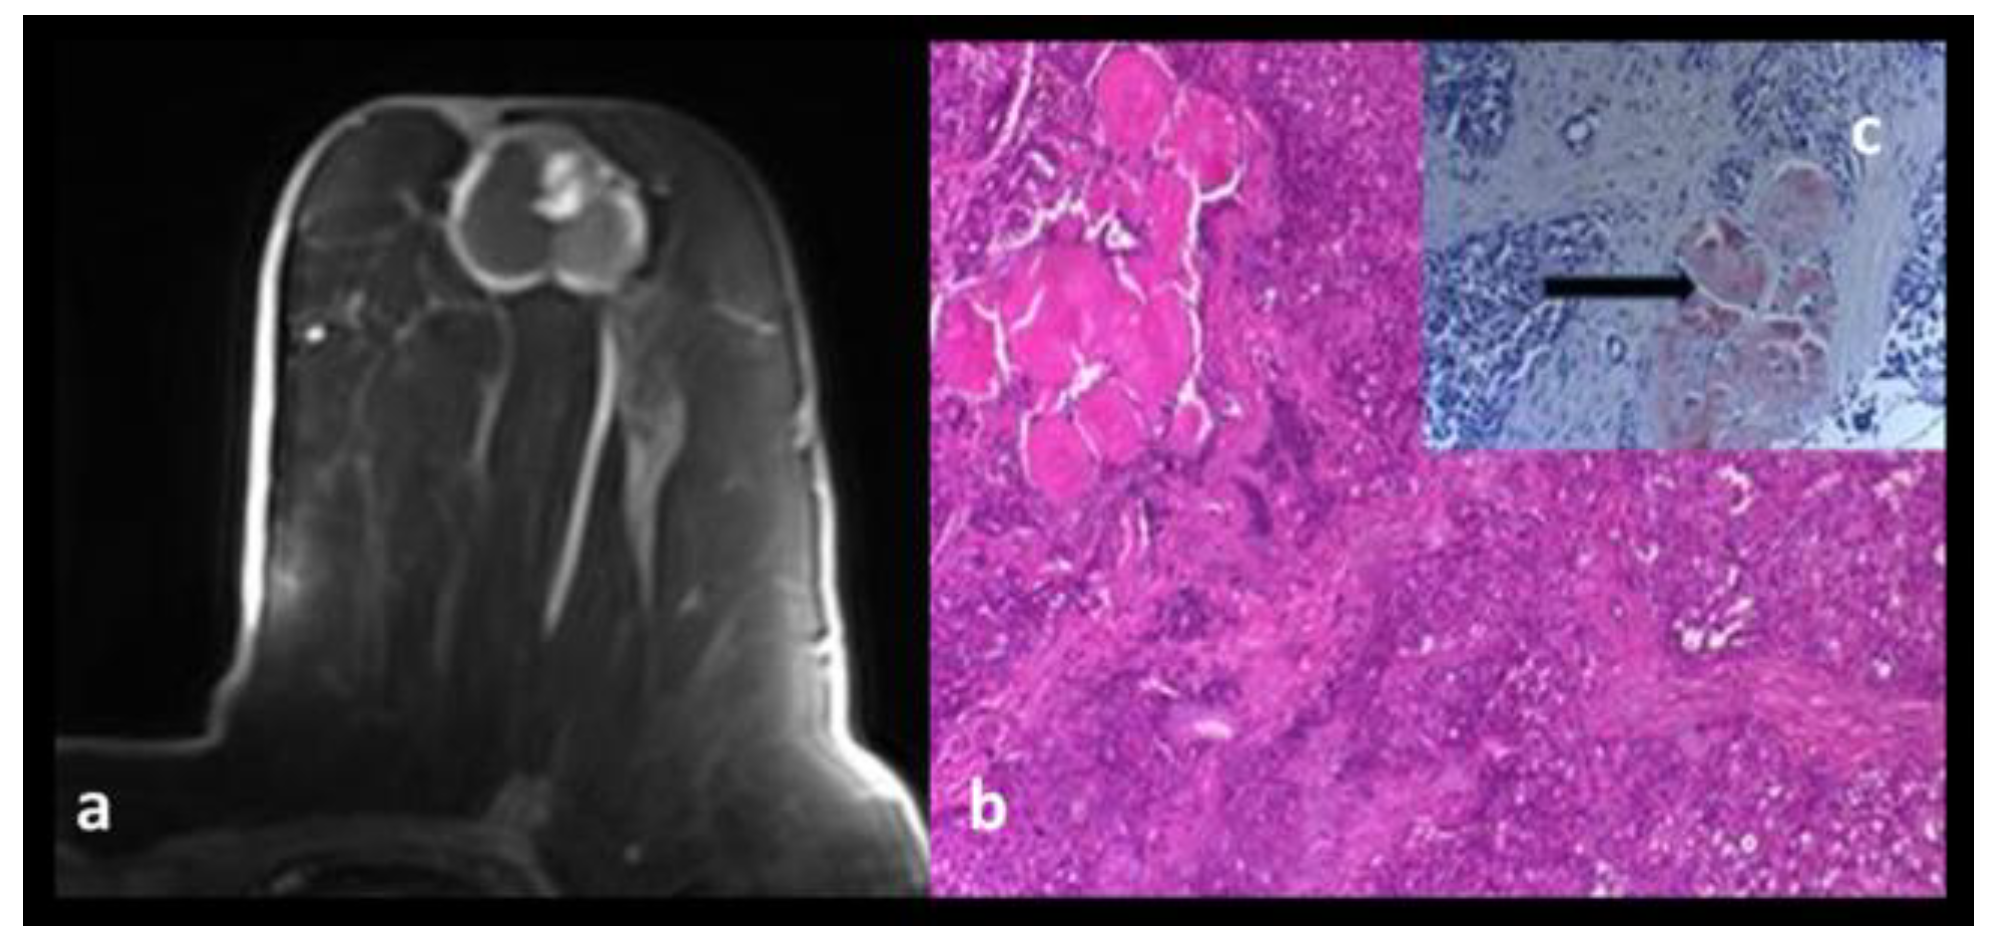

Adenomyoepithelioma